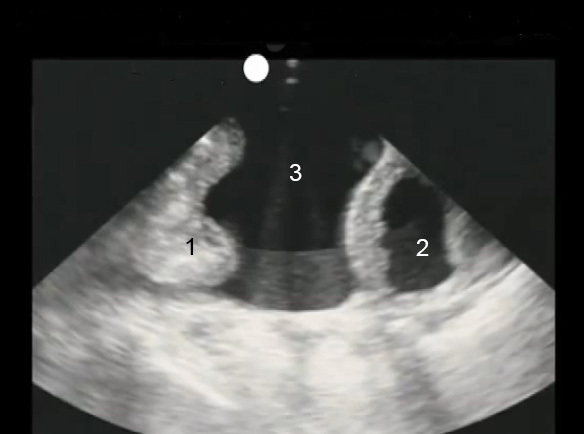

Paracentesis Linea Alba Image

Bowel

Bladder

Ascites